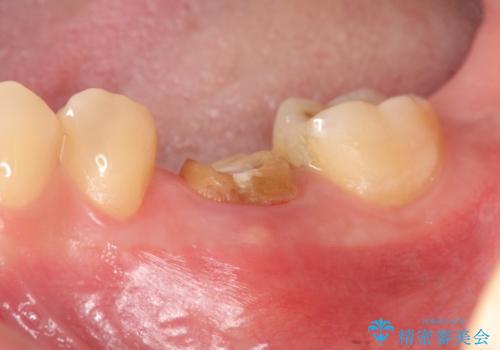

放置してしまった歯 根管治療からの機能回復

大きな虫歯で崩壊した歯の修復